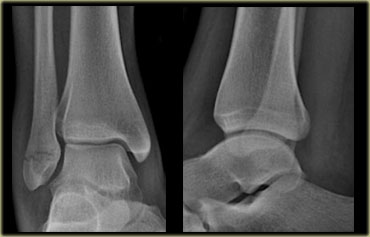

These images show another typical Weber B fracture stage 4.

There is an oblique fracture of the fibula.

There is an avulsion of the posterior malleolus and an avulsion of the medial malleolus.

Here another typical Weber B fracture stage 4.

First notice the oblique fibular fracture, which is best seen on the lateral view.

This is stage 2 and we have to assume, that the anterior syndesmosis is ruptured.

On the lateral view a small tertius fragment is seen indicating stage 3.

Now you start looking for stage 4 and you will notice the subtle lucency in the medial malleolus on the AP view (green arrow).

Knowing the stages of Lauge Hansen this must be a fracture.